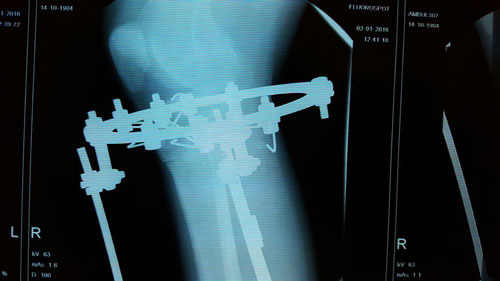

Дата операции 02.10.2015г.

Дата снятия аппаратов 04.01.2016г.

Срок лечения 90 дней.